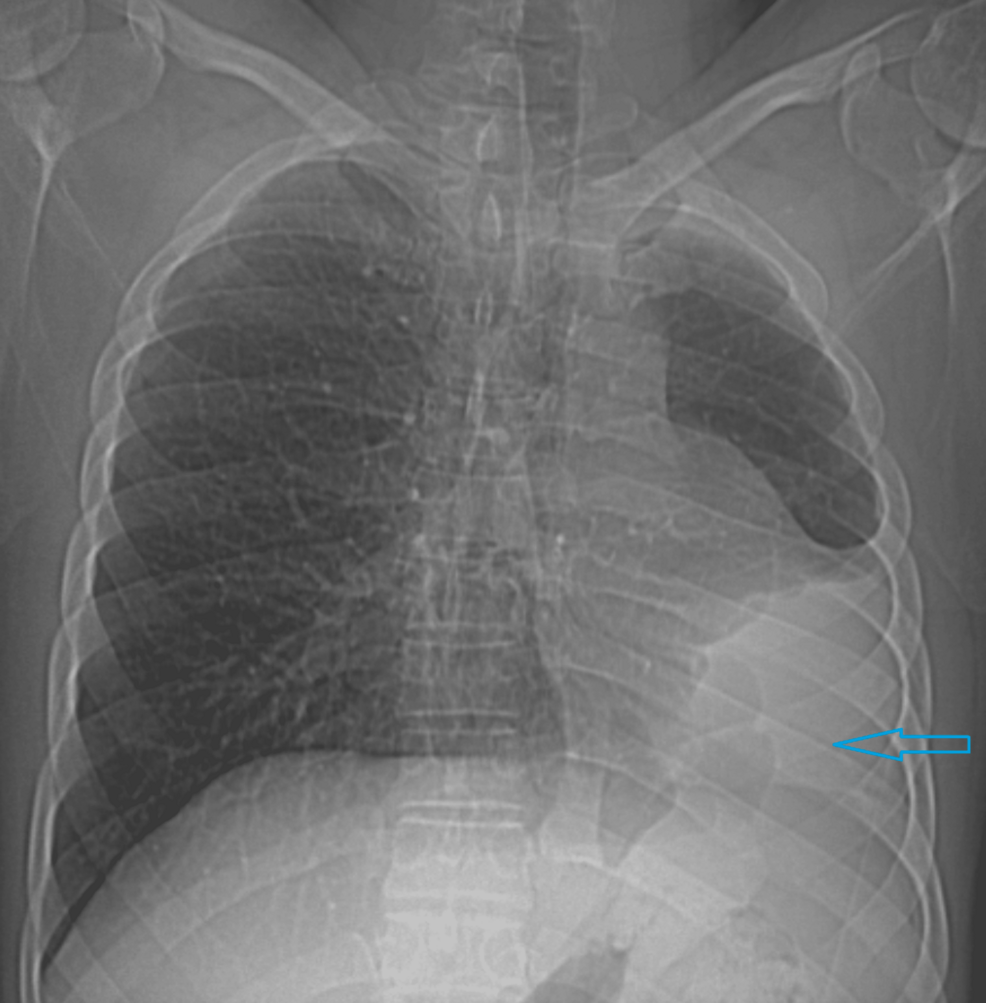

initial physical examination revealed decreased breath sounds on the left side of the chest.Auscultation was crucial in raising suspicion, prompting further investigation.Differential diagnoses considered included pneumothorax, pleural effusion, and lobar collapse. though, these were quickly ruled out by initial chest radiography.

The cornerstone of diagnosis for ILPA is complete imaging. While a chest X-ray may suggest the anomaly, it often lacks the detail needed for definitive confirmation.

A high-resolution CT scan of the chest was pivotal in confirming the diagnosis. The scan demonstrated:

- Complete absence of the left lung.

- Mediastinal shift to the left, with compensatory hyperinflation of the right lung.

- Displacement of the heart and great vessels towards the left hemithorax.

- Absence of the left pulmonary artery.